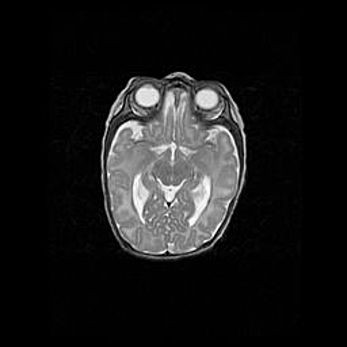

Мальформация Денди-Уокера. Киста задней черепной ямки.

Агенезия мозолистого тела.

Возраст: 2,5 месяца

Вес: 2420 г

Пол: женский

Окружность головы: 37 см

Срок гестации: 32 недели

Мальформация Денди—Уокера — редкий вид патологии ЦНС, представляющий собой врожденный порок развития каудального отдела ствола и червя мозжечка, ведущий к неполному раскрытию срединной (Мажанди) и латеральных (Лушка) апертур IV желудочка мозга. Для этогно синдрома характерна триада симптомов: гипотрофия червя мозжечка и/или полушарий мозжечка, кисты задней черепной ямки, гидроцефалия различной степени. В 70% случаев порок сочетается и с другими аномалиями головного мозга, в частности с агенезией мозолистого тела.